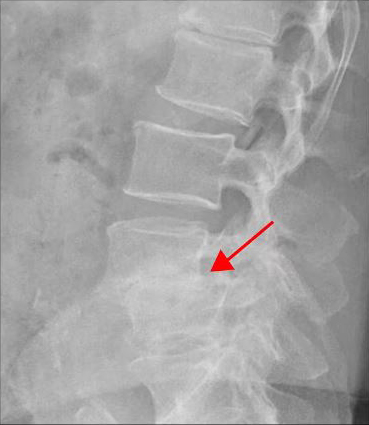

<5-1번 디스크 파열>

이 환자분은 요추 4-5번 오른쪽에 심한 추간공협착증, 2단계의 전방전위증이 있으며, 특히 전방전위증으로 인해 추간공이 매우 좁아져 있습니다. 또 요추 5-1번 왼쪽에 디스크 파열이 있습니다.